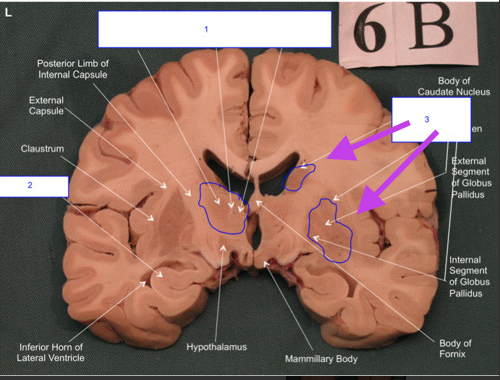

Basal Ganglia. Deep in the cerebral hemispheres of the cerebrum. Collection of gray matter.

Name #1

Corpus callosum. White matter.

32

Name #2

Lateral ventricles.

33

Name #3

Longitudinal fissure.

34

Name #4

Thalamus. Gray matter.

35

Name #5

Third ventricle.

36

Name #6

Substantia Nigra. gray matter.

37

Hippocampus. Gray matter in cerebral cortex.